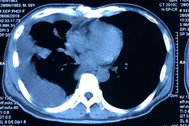

4 thói quen lành mạnh cần có khi điều trị ung thư phổi

(Dân trí) - Nếu đang chiến đấu với bệnh ung thư thì một lối sống lành mạnh có thể giúp bạn giữ được một sức khỏe tốt trong và sau khi điều trị.